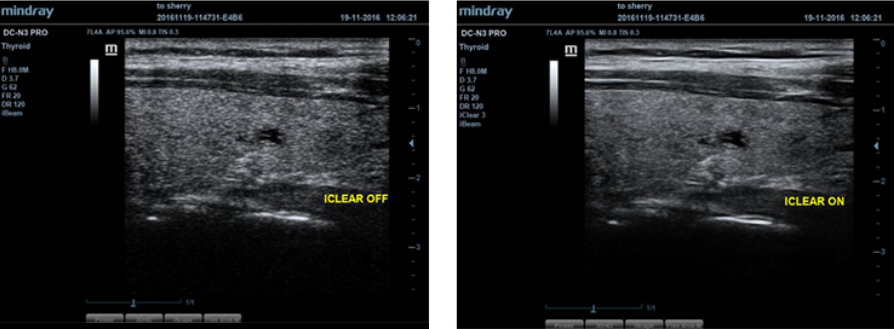

iClear?

Mejor calidad de imagen basada en la detecciĂłn automĂĄtica de estructuras.

- Bordes mĂĄs nĂtidos y continuos.

- Tejidos uniformes lisos.

- â?reas sin ecoâ mĂĄs limpias.